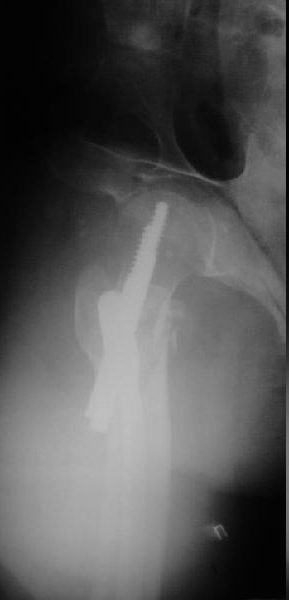

Это типичная проблема, вот аналогичный случай. Удалили, исправили,

фиксировали другим PFN.